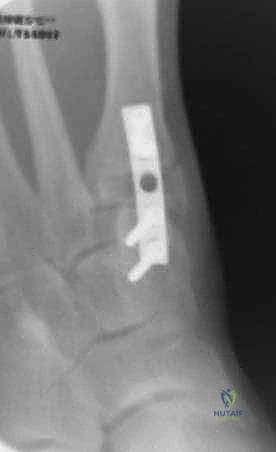

2. التصوير الشعاعي المتقدم

- الأشعة السينية مع تحمل الوزن (Weight-bearing X-rays): صور من الأمام، الجانب، والزوايا المائلة لتقييم زوايا العظام تحت تأثير وزن الجسم.

- تصوير السمسمانيات (Sesamoid view): لمعرفة ما إذا كانت العظام السمسمانية قد خُلعت من مكانها.

- الأشعة المقطعية (CT Scan): في الحالات المعقدة، يستخدم الدكتور هطيف الأشعة المقطعية ثلاثية الأبعاد لتقييم التئام العظام السابق، ومواقع المسامير القديمة، ودرجة خشونة المفاصل بدقة متناهية.

- يتم تحديد مواقع المسامير أو الشرائح المعدنية من الجراحة السابقة وإزالتها (Hardware Removal). قد تكون هذه الخطوة صعبة إذا نما العظم فوق المسامير.

ج. إيثاق مفصل المشط السلامي الأول (First MTPJ Arthrodesis)

يُعتبر هذا الإجراء "المعيار الذهبي" (Gold Standard) وجراحة الإنقاذ النهائية في حالات المراجعة المعقدة، خاصة إذا كان المريض يعاني من:

* تدمير المفصل أو خشونة شديدة (التهاب المفاصل العظمي).

* فقدان عظمي كبير من الجراحة السابقة.

* تكرار شديد للتشوه مصحوب بألم مبرح.

في هذه العملية، يتم إزالة الغضروف التالف من مفصل الإصبع الكبير، ودمج العظام معًا في وضع مستقيم قليلاً للأعلى للسماح بالمشي الطبيعي. يتم التثبيت باستخدام شريحة ومسامير متقاطعة. النتيجة هي إصبع مستقيم، خالٍ تمامًا من الألم، ولا يمكن أن يعود للتشوه أبدًا.